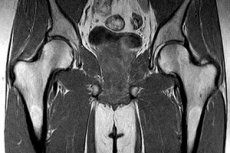

A combcsont MRI-vizsgálata: mit mutat, mikor írják fel, hogyan végzik el

A combcsont mágneses rezonancia képalkotása nemcsak a csont külső kontúrját, hanem a csontvelőt, a trabekuláris struktúrát, a csonthártyát, a szomszédos izmokat, inakat, érrendszeri és gyulladásos elváltozásokat is megjeleníti. Ez különösen hasznossá teszi, ha a hagyományos radiográfia még nem mutatott ki semmi meggyőzőt, de fájdalom, korlátozott teherbírás vagy súlyos patológia gyanúja már fennáll. Csontvelő esetében a mágneses rezonancia képalkotást tekintik a választott módszernek, mivel érzékeny a szövetösszetétel és a beszűrődés korai változásaira. [1]

A gyakorlatban ennek a vizsgálatnak három különböző célja lehet. Az első a proximális combcsont, azaz a fej, a nyak és a trochanter régió vizsgálata, ahol a stresszes sérüléseket, az oszteonekrózist és az okkult töréseket keresik leggyakrabban. A második a diafízis értékelése, amikor daganat, áttét, fertőzés vagy csontvelő-elváltozás gyanúja merül fel. A harmadik a térdízület közelében lévő disztális combcsont vizsgálata, ahol a csontvelőödéma, a porc alatti elváltozások és a daganatos folyamatok fontosak. [2]